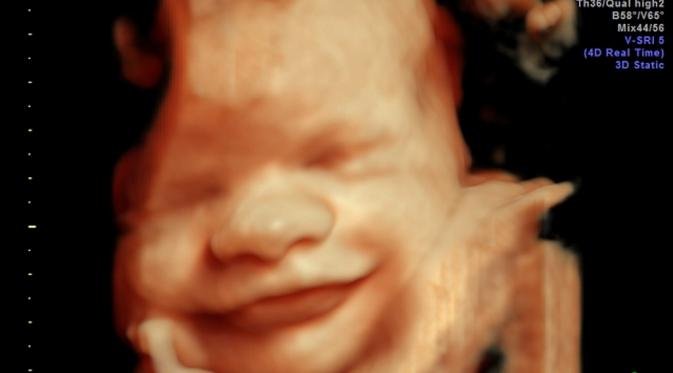

Di USGHaloBunda, kamu bakal dapet pemeriksaan dengan teknologi USG terbaru yang bisa kasih gambaran lebih jelas dan akurat tentang perkembangan janin. Pake teknologi canggih kayak USG 2D, 3D, dan 4D, kamu bisa lihat wajah bayi bahkan sebelum lahir!